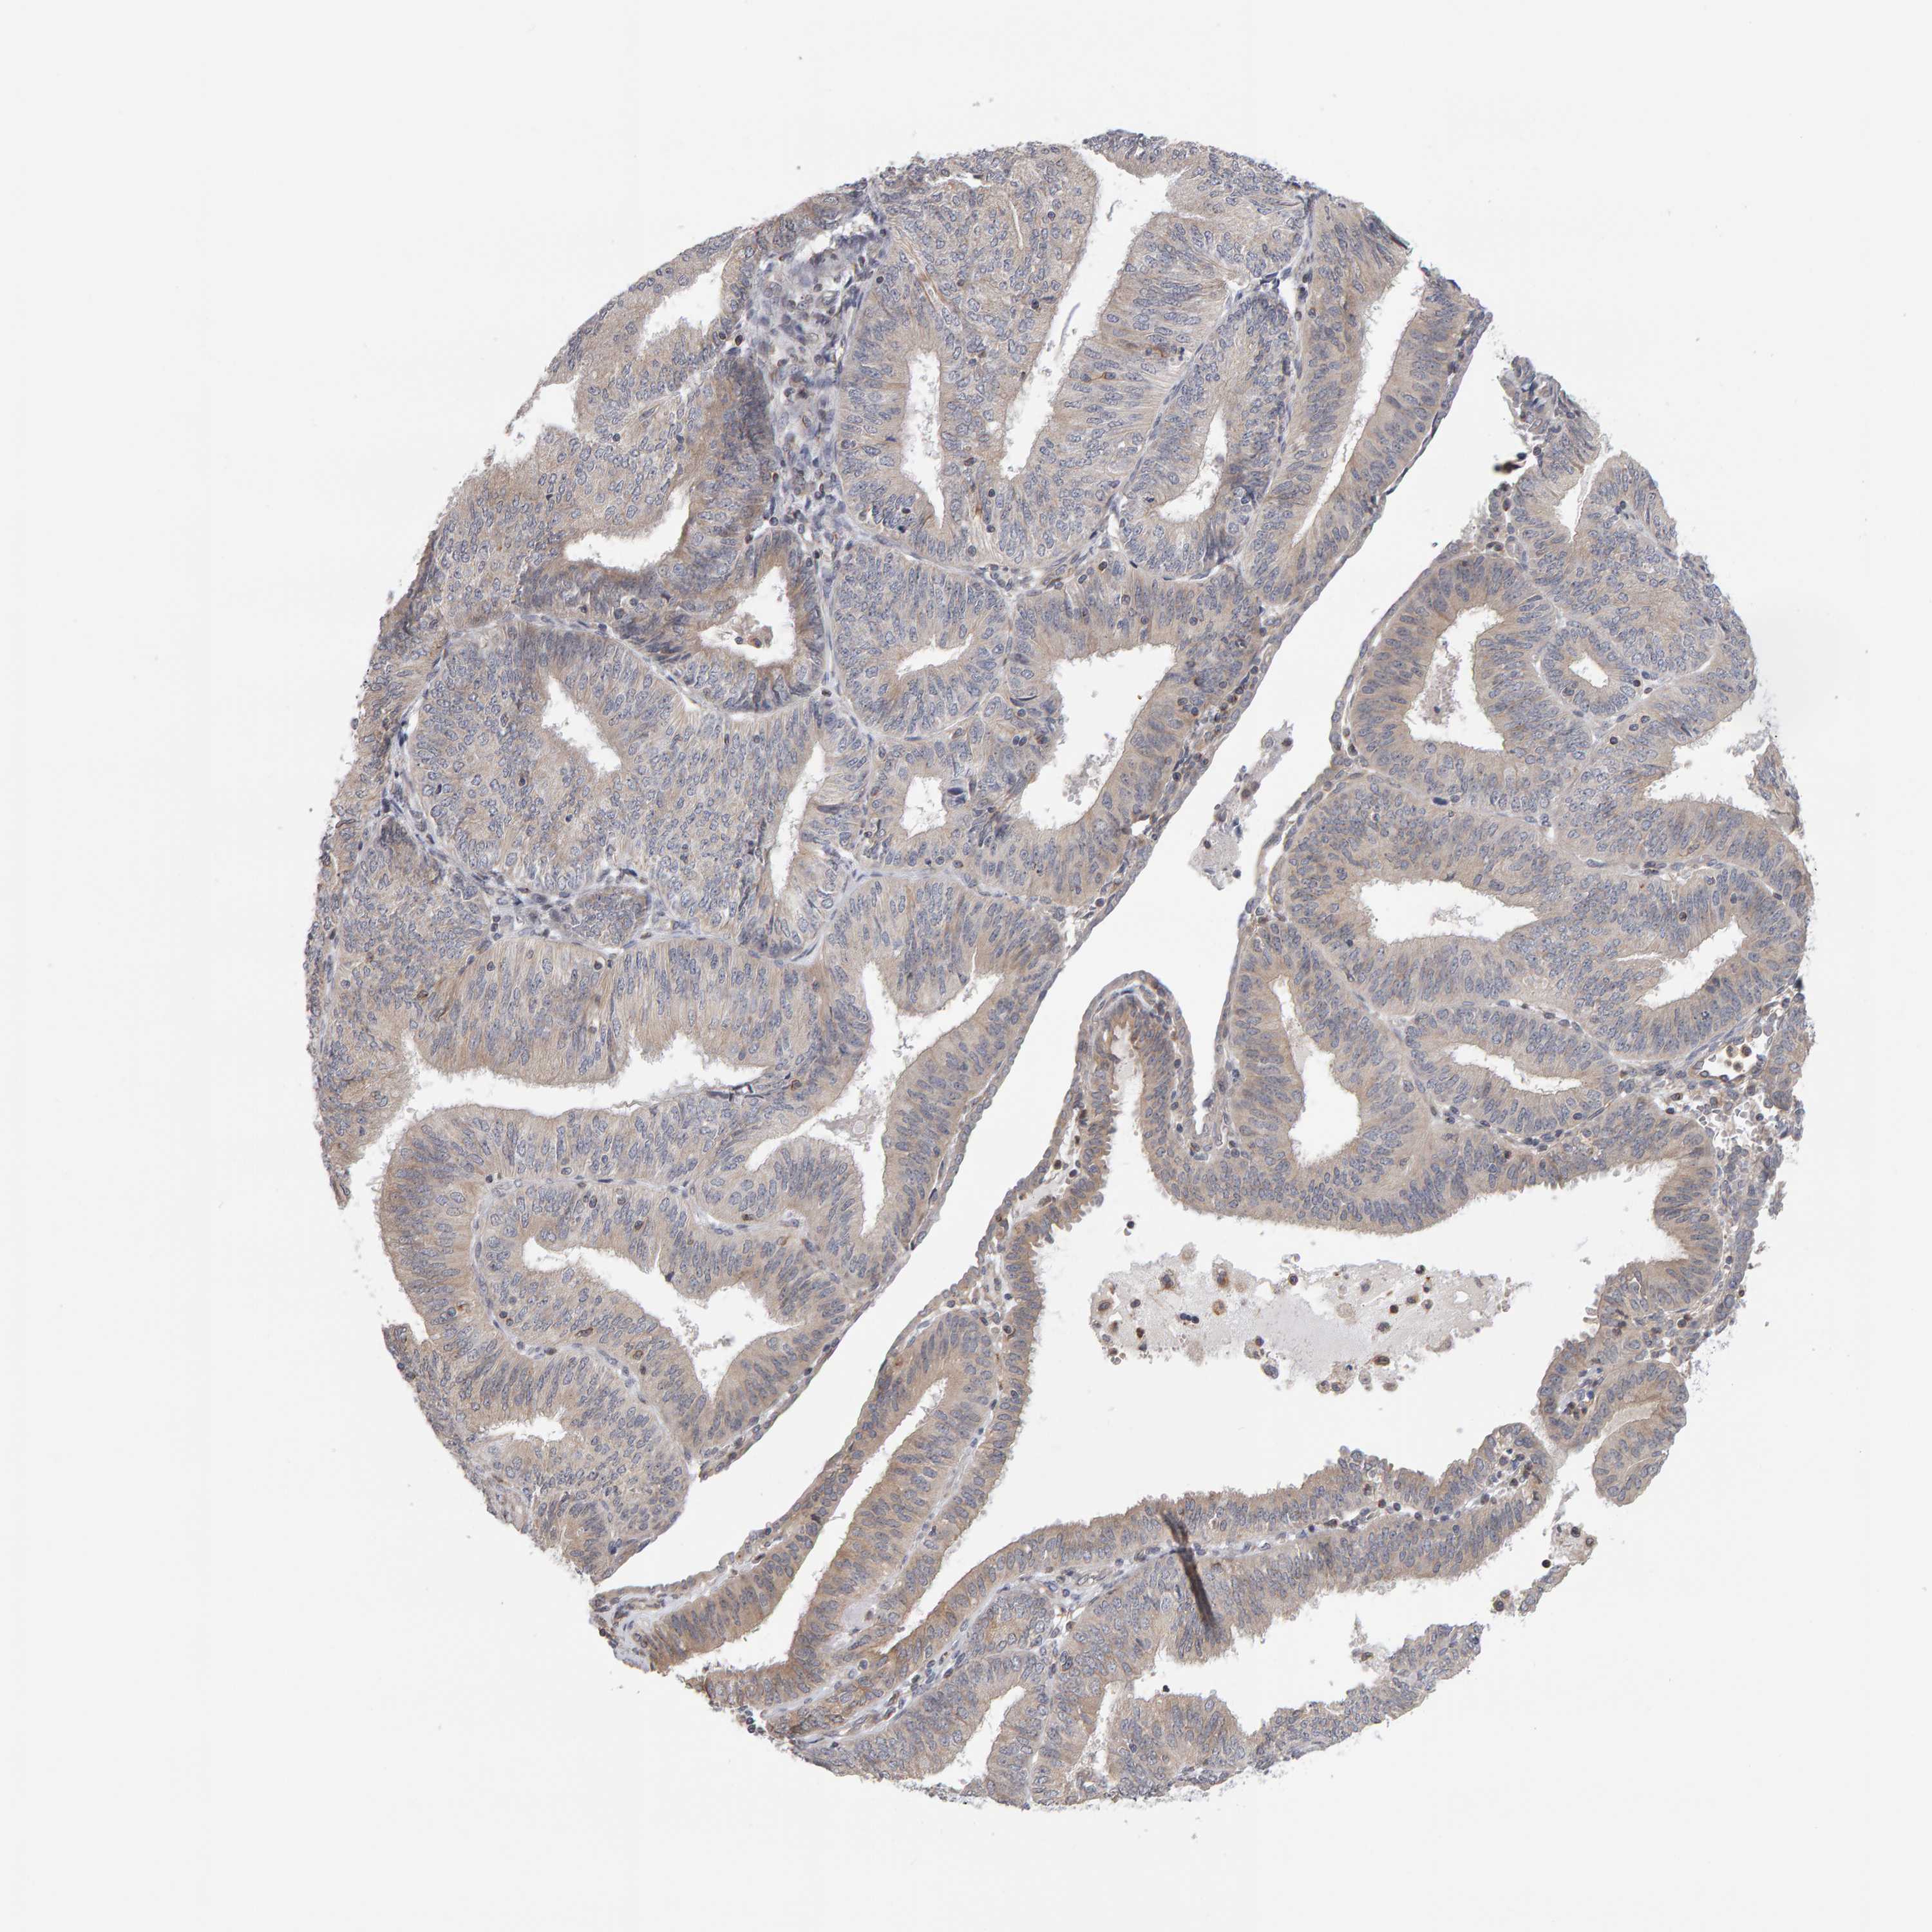

ENDOMETRIAL CANCER - Protein expressioni

A mouse-over function shows sample information and annotation data. Click on an image to view it in a full screen mode. Samples can be filtered based on level of antibody staining by selecting one or several of the following categories: high, medium, low and not detected. The assay and annotation is described here.

Note that samples used for immunohistochemistry by the Human Protein Atlas do not correspond to samples in the TCGA dataset.

Antibody stainingi

Antibody staining in the annotated cell types in the current human tissue is reported as not detected, low, medium, or high, based on conventional immunohistochemistry profiling in selected tissues. This score is based on the combination of the staining intensity and fraction of stained cells.

Each image is clickable and will lead to virtual microscopy that enables deeper exploration of all samples and also displays staining intensity scores, fraction scores and subcellular localization as well as patient and tissue information for each sample.

Antibody HPA023804

Antibody HPA075766

Staining

High

Medium

Low

Not detected

Intensity

Strong

Moderate

Weak

Negative

Quantity

>75%

75%-25%

<25%

None

Location

Nuclear

Cytoplasmic/membranous

Cytoplasmic/membranous,nuclear

Adenocarcinoma, NOS

Adenoma, NOS